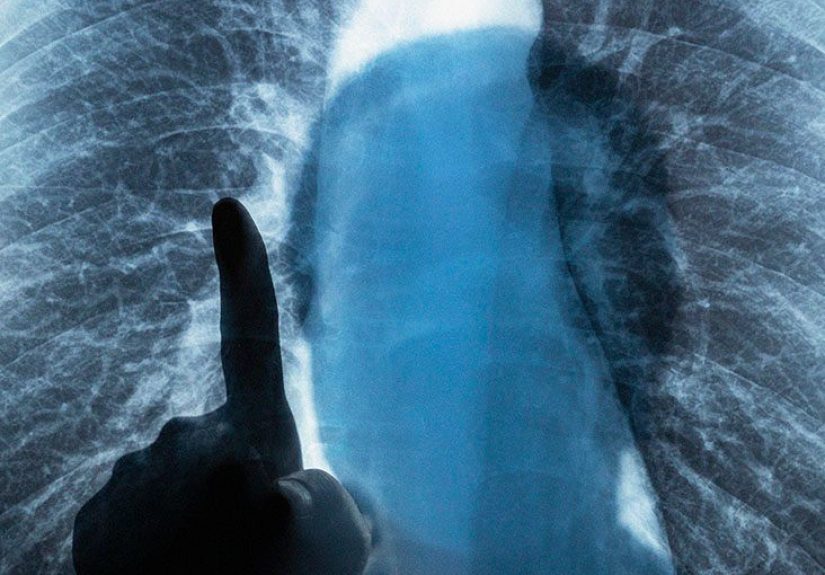

- Pulmonary testing: spirometry, diffusion capacity, oxygen needs, and exercise capacity (often with a 6-minute walk test).

- Imaging: CT scans and other studies to understand anatomy and disease pattern.